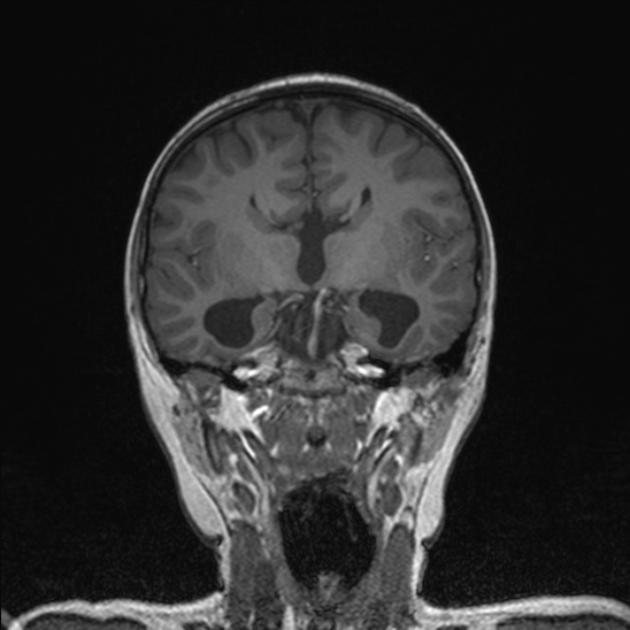

O sinal do alce (moose signal) ou sinal do capacete viking (viking helmet signal) pode ser observado na neuroimagem em indíviduos com digenesia/agenesia do corpo caloso ou desmielinização. Na ressonância magnética em corte frontal, os ventrículos laterais apresentam-se tal qual a cabeça de um alce, e o giro cingulado é evertido em longos e estreitos chifres.